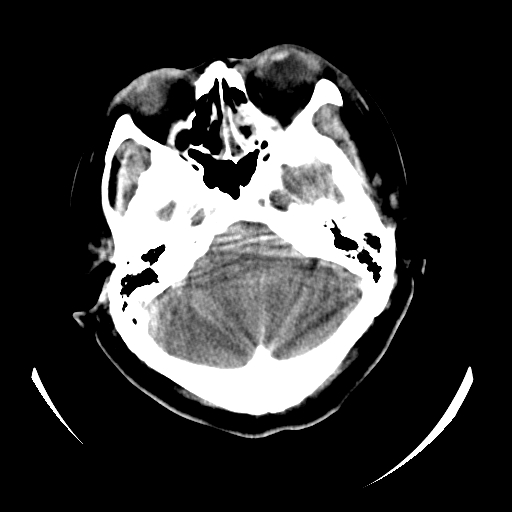

女,53岁,发现昏迷1天,血压不高,有精神病史。临床诊断:脑梗死?

ct诊断:1、双侧基底节区对称性脑梗塞。

2、双侧额叶、枕叶广泛密度减低,考虑缺血梗塞可能性大。

3、脑池小,脑沟浅,提示颅内高压。

测左枕叶白质ct值 约22hu 。请各位老师给出恬当诊断。

征象:病变呈对称性分布于双侧大脑半球,累及范围广泛,白质较灰质密度减低更为明显;脑沟变浅,脑池变窄;